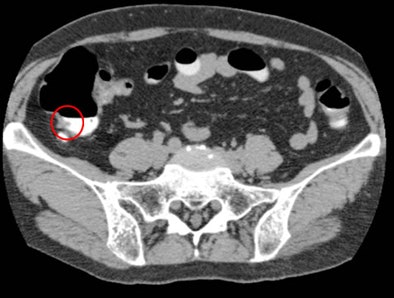

Polyp locations were assigned to one of six colonic segments: rectum, sigmoid colon, descending colon, transverse colon, ascending colon, and cecum. Locations other than the cecum were further noted as proximal, mid, or distal within each segment. Polyp size was measured on 2D images using an electronic ruler, and the final diagnosis was made by consensus of the readers.

In the same-day preparation group, per-polyp sensitivities of the gastroenterologist and the radiologist were 91% and 73%, respectively, for polyps 6-9 mm. Per-polyp sensitivities in the reduced bowel preparation group were 86% and 86%, respectively, for polyps 6-9 mm. In both preparation regimens, sensitivities of the two readers were 100% for polyps 10 mm or larger, Nagata and his colleagues reported.

In the same-day preparation group, false-positive findings per patient for the gastroenterologist and the radiologist were 0.15 and 0.1, respectively, while those in the reduced bowel preparation group were 0.3 and 0.2, respectively.